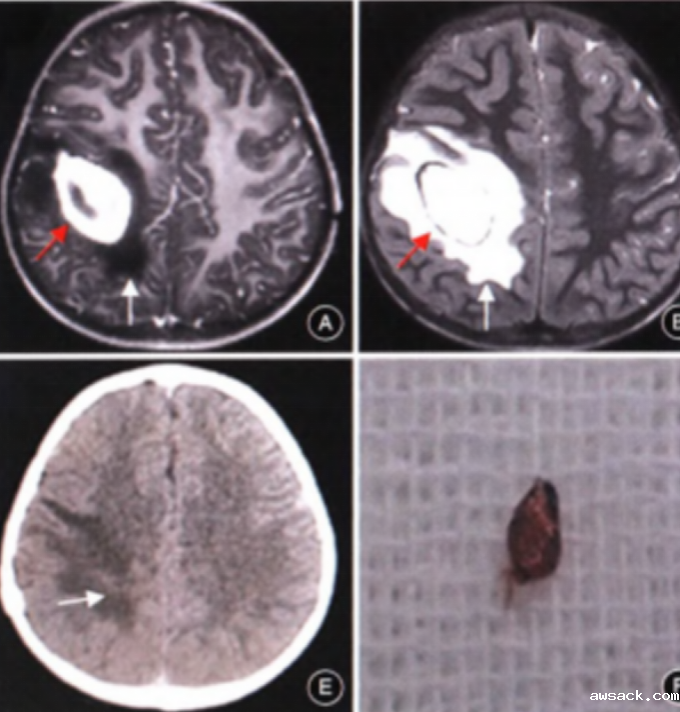

7.小骨窗显微手术是治疗儿童脑型肺吸虫病的有效方法,具有缩短手术时间,显微镜下顺利寻找病灶边界,减少对周围正常脑组织的牵拉。手术创伤小、恢复周期短,做到对脑组织及周围神经损伤最小。